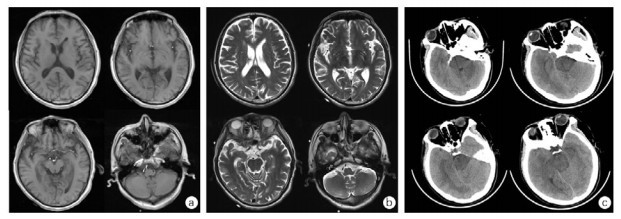

| 摄入虫螨腈后131 h病例1颅脑磁共振T1WI(A)、T2WI(B):两侧大脑半球对称,灰白质对比良好,两侧侧脑室旁多发小片状长T1、长T2信号。摄入虫螨腈后230 h病例2颅脑CT图像(C):脑干密度减低,脑白质水肿,全脑肿胀 图 3 摄入虫螨腈后患者颅脑影像学检查 Fig 3 Cerebral imaging of patients after ingestion of chlorfenapyr |

1 资料与方法 1.1 治疗经过病例1是一名70岁男性,因“口服甲维虫螨腈(甲氨基阿维菌素1%,虫螨腈5%)20 mL, 10 h”入院,虫螨腈含量1 g。患者自服杀虫剂5 h后在当地医院予清水500 mL催吐1次。摄入10 h后转至本院,入室查体:T 36.8℃,P 98次/min,R 20次/min,BP 138/83 mmHg,SpO2 97%,心肺腹部均无异常。初步诊断:急性杀虫剂中毒(虫螨腈)。给予乳果糖90 mL、复方聚乙二醇电解质散1 000 mL、20%甘露醇250 mL口服导泻,30%脂肪乳250 mL静脉滴注。摄入毒物后13 h、16 h、38 h、41 h、60 h、63 h共行6次(2次/ d×3 d)血液灌流,动态监测血液中虫螨腈及代谢产物溴代吡咯腈浓度(见图 1A)。摄入毒物后185 h,患者出现一过性体温升高,最高38.0℃(见图 2A),并伴有四肢肌张力增高。第9天患者自动出院,出院后3 d随访无异常,其后失访(通过多种方式未查证到患者死亡信息)。在入室、首次血液灌流1 h、2 h、12 h后,以及灌流3次后、入室第5天、第7天共7个时间点,分别留取EDTA抗凝血2 mL。(住院期间实验室检查见表 1,颅脑影像学检查见图 3A、B)。

病例2是一名40岁女性,因“口服虫螨腈虱螨脲(虫螨腈9.5%,虱螨脲2.5%)250 mL 149 h”入院,虫螨腈含量23.75 g。患者自服杀虫剂后家属立即予以催吐1次,摄入毒物后2 h即感全身燥热、多汗。患者拒绝洗胃,当地医院未予特殊治疗。149 h后转至本院,入室查体:T 36.5℃,P 75次/min,R 18次/min,BP 99/67 mmHg,SpO2 98%,神志清楚,心肺腹部均无异常。初步诊断:急性杀虫剂中毒(虫螨腈)。予30%脂肪乳250 mL静脉滴注、血液灌流2次/ d×2 d共4次、持续性血液透析滤过(continuous veno-venous hemodiafiltration, CVVHDF)治疗85 h,动态监测血液中虫螨腈及溴代吡咯腈浓度(见图 1B)。摄入毒物203 h患者出现烦躁、谵妄,230 h转为昏迷状态。237 h患者突发呼吸停止,血压下降至54/36 mmHg,双瞳直径散大至3.5 mm,立即予经口气管插管、机械通气,同时积极抗休克治疗,血压难以维持,患者于摄入247 h后死亡。在入室、首次血液灌流后、第二次灌流后,发病第7、8、9天的6:00和18:00共9个时间点,分别留取EDTA抗凝血2 mL。(住院期间实验室检查见表 1,颅脑影像学检查见图 3C)。